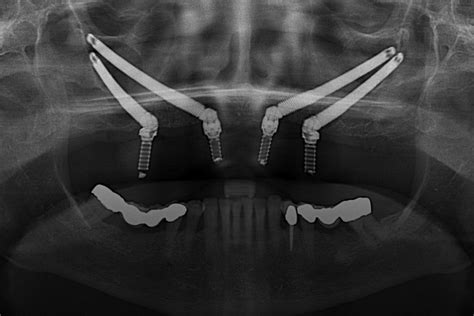

Implantes cigomáticos: la opción para los huesos rebeldes

Esto ya es nivel experto. Si has perdido tanto hueso en el maxilar superior que no hay dónde agarrarse, ni siquiera con injertos, aquí entran en juego los implantes cigomáticos. ¿La diferencia? Se fijan al hueso cigomático, que es el del pómulo. Es más fuerte, más profundo y no se reabsorbe como el maxilar.

¿Qué los hace distintos? Son más largos, van colocados en ángulo y requieren una cirugía con experiencia. No todas las clínicas los hacen. Es un procedimiento más técnico y con menos margen para errores.

¿Cuándo están indicados?

- Cuando no queda prácticamente nada de hueso en el maxilar.

- Si ya has pasado por otros tratamientos sin éxito.

- Cuando quieres evitar una reconstrucción ósea extensa.

Lo mejor de este tipo de implante:

- No necesitas injertos ni esperar meses.

- Se puede hacer carga inmediata en muchos casos (te vas con dientes provisionales puestos).

- Resuelve situaciones complejas de una forma estable.

💰 Precio: desde 3.000 hasta 4.000 euros por unidad.